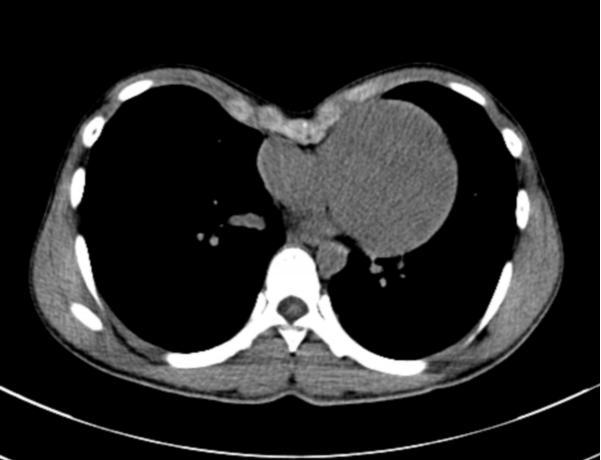

20岁小向(化名)胸前区凹陷畸形已有多年,被诊断为重度漏斗胸,心脏明显受压移位。小向今年已是大一学生,之前自己及家长对他胸前区的凹陷一直没有重视,上大学后自觉胸廓凹陷对其日常生活的困扰越来越显著并存胸闷不适,在了解到其胸廓畸形可手术治疗后经多方打听慕名来到我院就诊。就诊时的胸部CT显示:胸前区明显凹陷,凹陷最低点距离脊柱前缘5cm左右,心脏明显受压向左移位。

术前CT显示胸前区凹陷畸形导致心脏明显受压移位

术前术后对比,胸前区凹陷畸形得到明显的改善